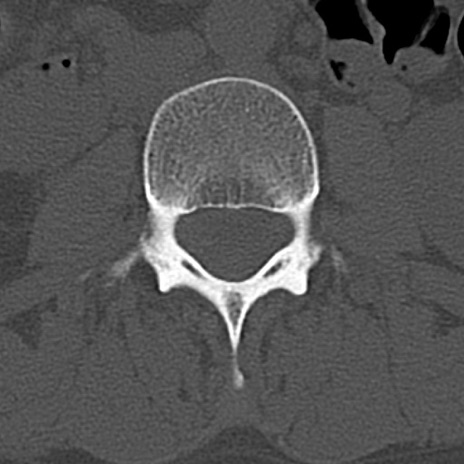

【整形】TIPS症例4 腰椎CT(横断像)

腰椎CT

横断像と矢状断像